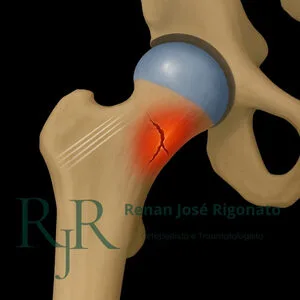

Fraturas por estresse

Lesão por sobrecarga, comum em corredores. Inicia com dor discreta e evolui sem trauma específico.

Fraturas do fêmur

As fraturas do fêmur proximal acontecem principalmente no colo do fêmur e região transtrocanteriana. Ambas exigem tratamento imediato.